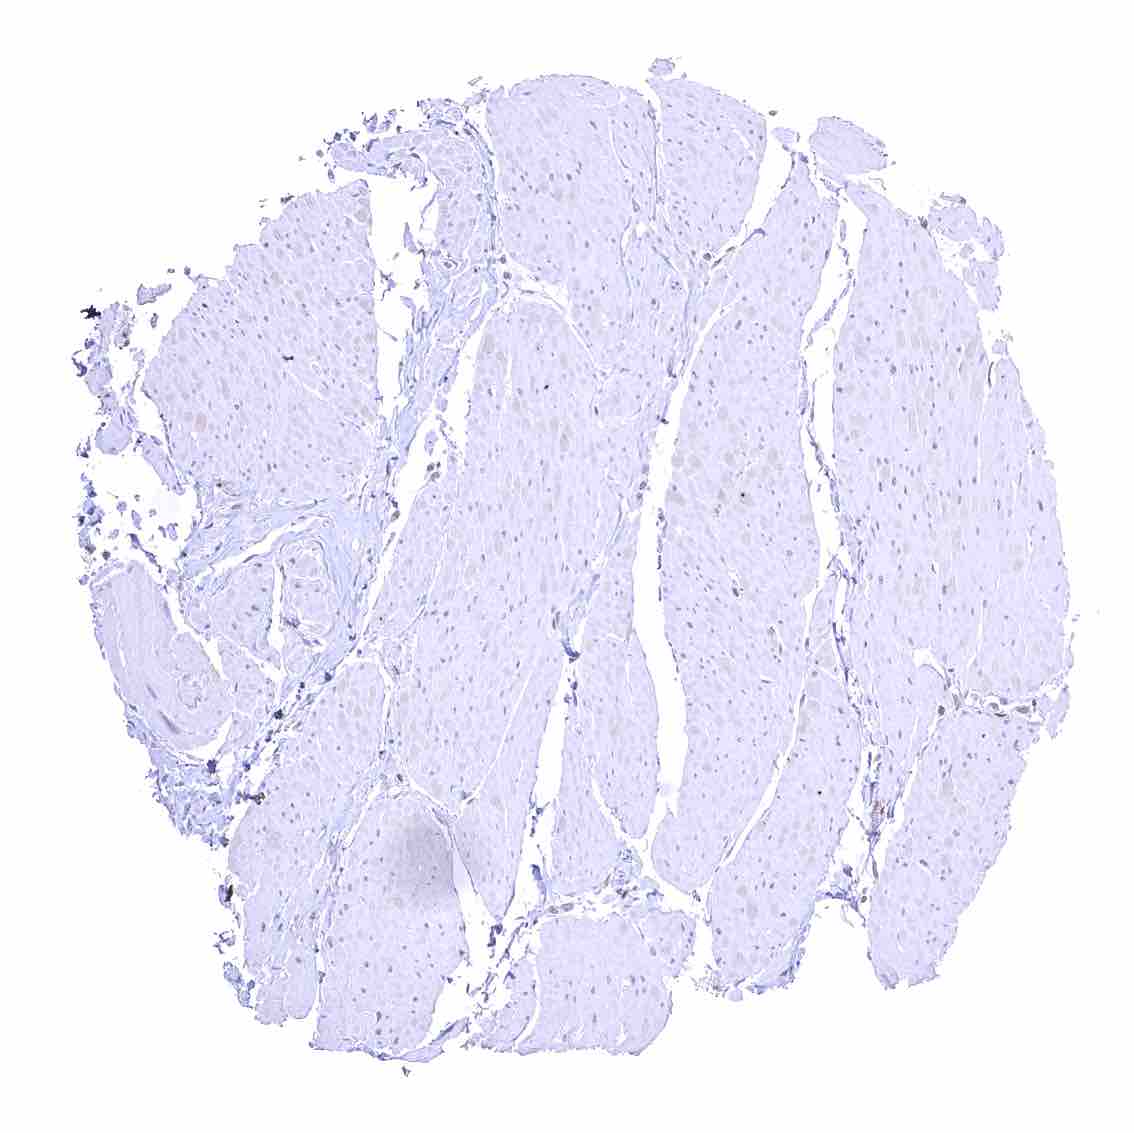

Heart muscle – Distinct nuclear p27 staining of stroma cells while myocytes are largely negative.